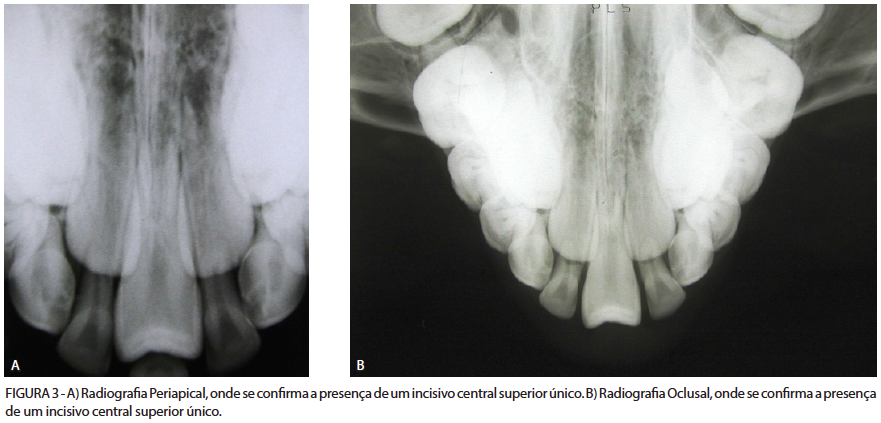

A paciente R. R., com 8 anos e 3 meses de idade, do gênero feminino, leucoderma, brasileira, apresentou-se ao setor de Triagem da Clínica Integrada Odontológica Infantil da Universidade Federal de Santa Maria – RS para avaliação. Após o exame clínico inicial, a paciente foi selecionada e encaminhada ao setor de Ortodontia da Clínica Infantil. Uma vez integrada à Disciplina de Ortodontia desta Clínica, a paciente foi devidamente assistida, tendo sido realizado o preenchimento da anamnese, das fichas de exames físico-clínicos e solicitado a documentação ortodôntica necessária para o adequado diagnóstico e tratamento da maloclusão. Ao exame clínico foi observada, como alteração bastante significativa, a presença de um incisivo central superior único, caracterizando um quadro de SICSS, além de atresia maxilar, como demonstram as figuras 1, 2 e 3.